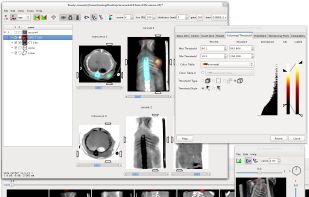

Weasis is a multipurpose standalone and web-based DICOM viewer with a highly modular architecture. It is a very popular clinical viewer used in healthcare by hospitals, health networks, multicenter research trials, and patients.

Weasis is a multipurpose standalone and web-based DICOM viewer with a highly modular architecture. It is a very popular clinical viewer used in healthcare by hospitals, health networks, multicenter research trials, and patients.